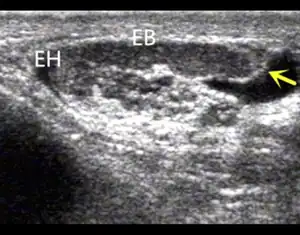

Scrotal ultrasonography and transrectal ultrasonography (TRUS) are useful in detecting uni- or bilateral CAVD, which may be associated with visible abnormalities or agenesis of the epididymis, seminal vesicles or kidneys.[10]